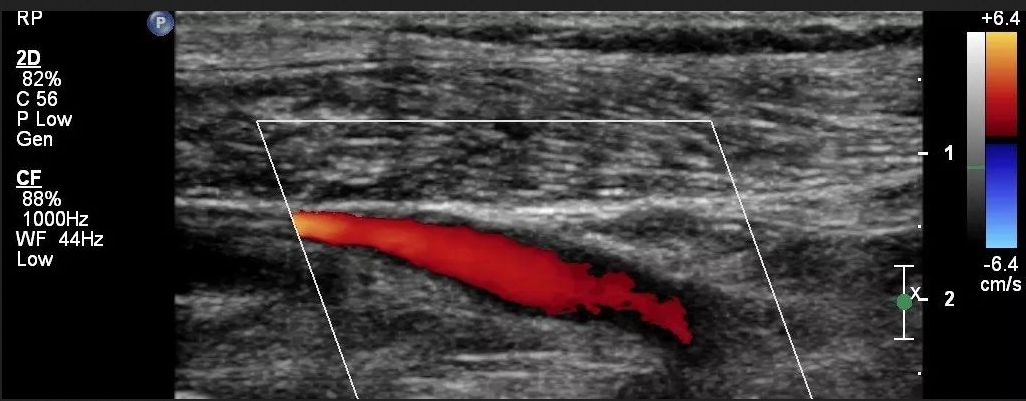

什么是彩色多普勒超聲?彩色多普勒超聲又稱彩超,是一種醫(yī)療設備,適用于全身各部位臟器超聲檢查尤其適用于心臟、肢體血管和淺表器官以及腹部、婦產(chǎn)等檢查診斷。它是以脈沖波多普勒為基礎,用運動目標顯示器,自相關函數(shù)計算,數(shù)字掃描轉(zhuǎn)換、彩色編碼等技術達到對血流的彩色顯像。

1、判斷血流方向

①彩色多普勒超聲中顯示的紅色不一定是動脈,而藍色也不一定是靜脈。

②常規(guī)情況下,紅色代表的是朝向探頭的血流,藍色代表背離探頭的血流。

當然,紅色代表朝向探頭,藍色代表背離探頭并不是一成不變的,可以通過機器進行設置。另外彩色多普勒取樣框的角度也可以改變血流顯示的顏色,但為了更好的呈現(xiàn)彩色血流信號,取樣框與血管角度應盡可能小。

2、初步判斷血流速度快慢

彩色多普勒信號強度可以粗略反映血流的快慢,彩色信號明亮說明血流速度快,彩色信號暗淡說明血流速度慢。

3、識別動脈與靜脈

在實際工作中需要鑒別動脈和靜脈的方法有很多,其中頻譜多普勒是我們常使用的方法之一,那么沒了頻譜多普勒,僅依靠彩色多普勒超聲我們該如何鑒別呢?

①由于動脈具有搏動性,其在舒張期血流速度慢而呈較暗淡的血流信號甚至無血流信號,而收縮期血流速度較快,呈較明亮的血流信號,在動態(tài)觀察時,便可見動脈血流信號呈閃動出現(xiàn),彩色信號較明亮。

②靜脈血流速低,無收縮期、舒張期之分,因此血流信號是連續(xù)出現(xiàn)的,彩色信號較暗淡。

4、判斷血流性質(zhì)

血流的性質(zhì)包括層流及湍流。層流的彩色血流信號顯示比較均勻,呈中央部亮度高、近管壁處亮度低的彩色信號;湍流則呈現(xiàn)五彩鑲嵌的血流信號等。